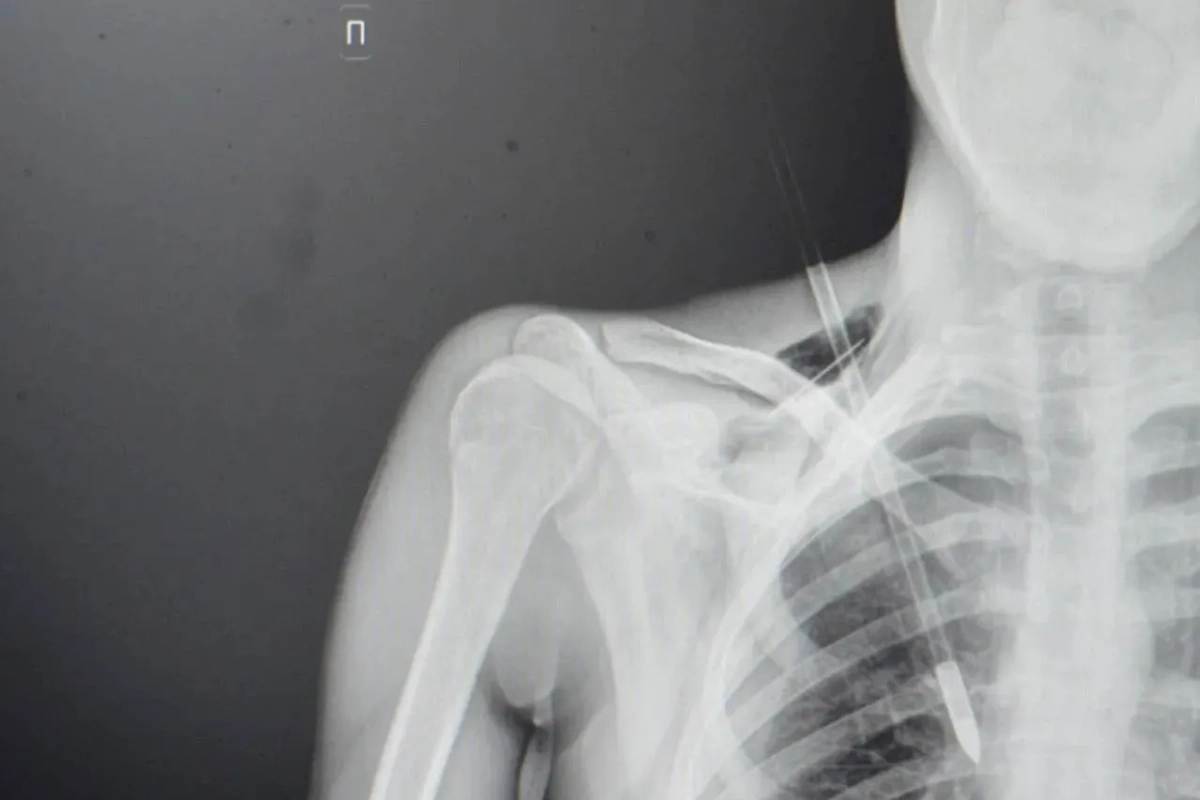

Стрела в грудной клетке. Фото © Министерство здравоохранения Московской области

Стрела прошла между ключицей и первым ребром, повредила верхушку лёгкого на шесть сантиметров, но крупные сосуды остались целыми. Пострадавшего срочно прооперировали: стрелу извлекли, повреждённое лёгкое ушили, а плевральную полость дренировали.